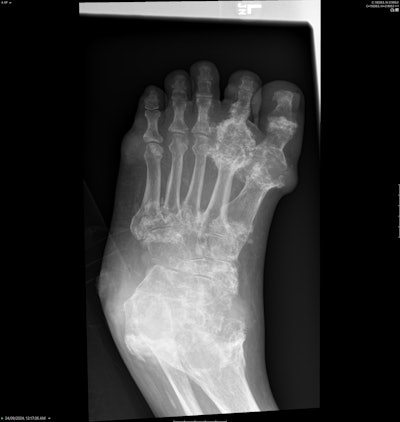

Diffuse juxta-articular erosions with overhanging edges and preserved joint spaces. Most marked at the first metatarsophalangeal joint (MTPJ) and ulnar styloid. All figures courtesy of Dr. Roland Zhang and presented at RANZCR 2025 ASM.

Similar findings of tophaceous gout in typical locations, such as the first MTPJ.